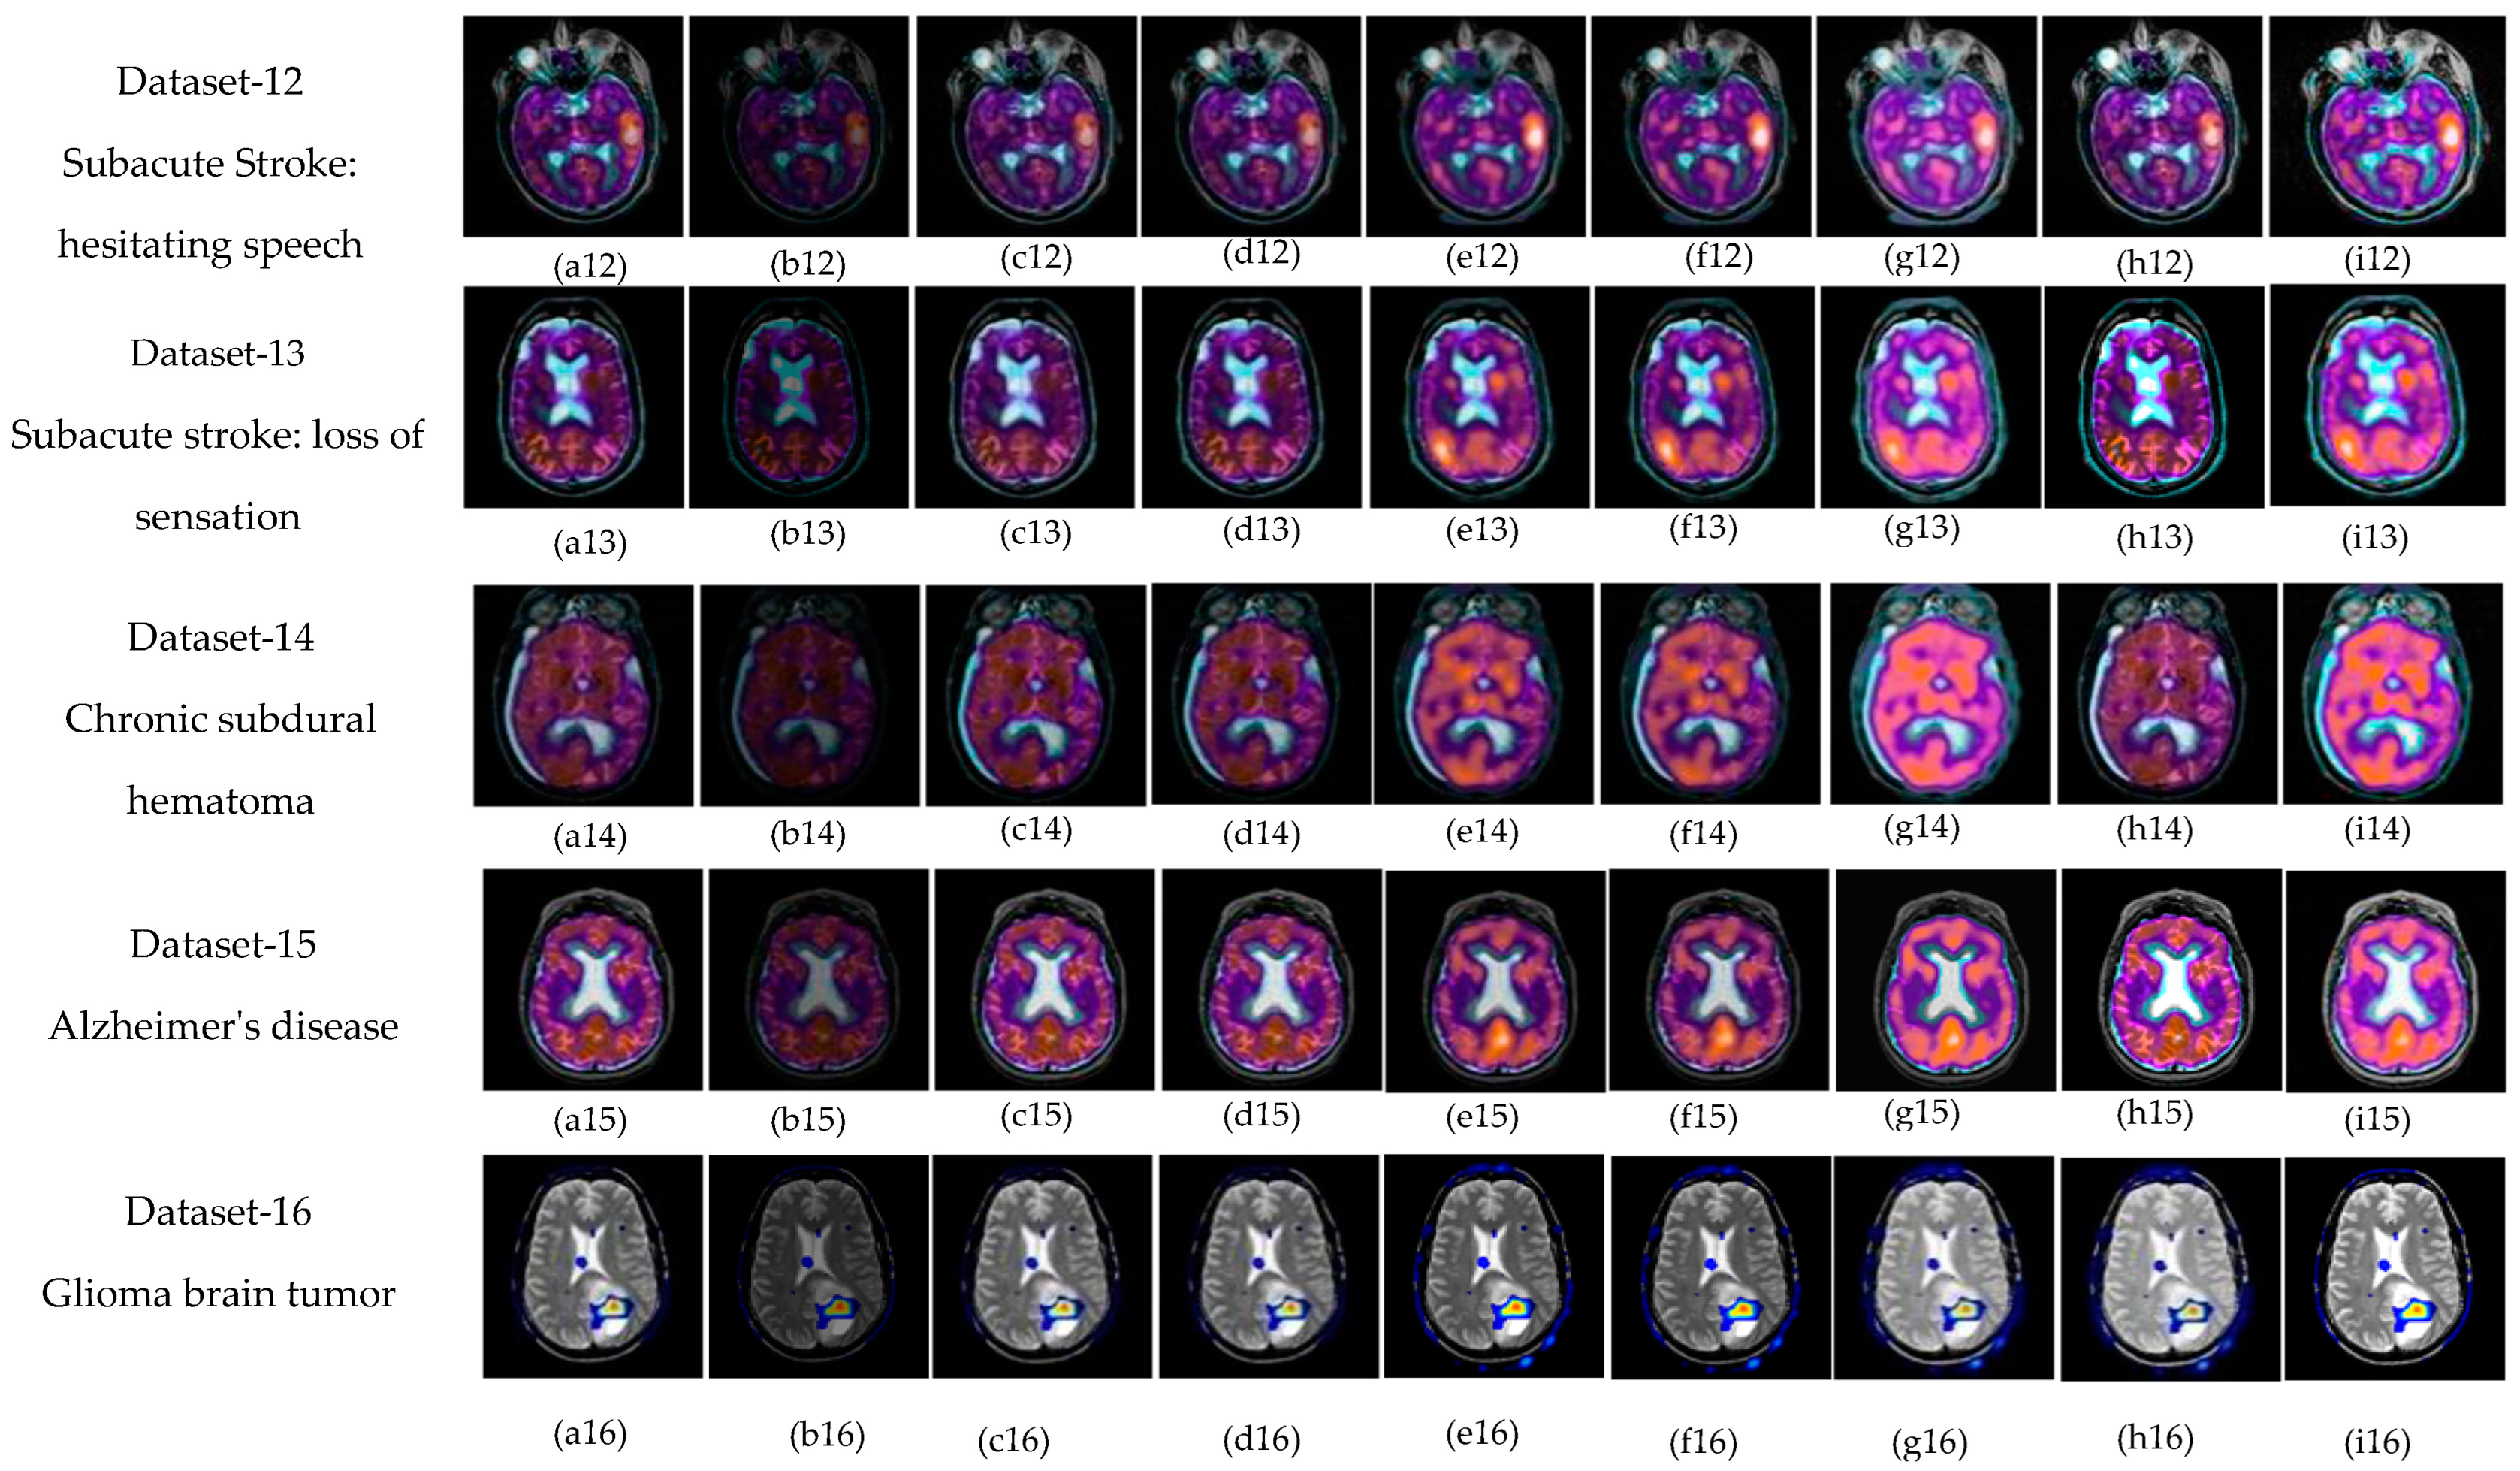

The subjective evolution is carried out on various input datasets as shown in Figure 3. In this paper, five groups of datasets have been used. The group 1 input images are MR-T1–MR-T2 datasets as shown in Figure 3((p1–p4) and (q1–q4)). Group 2 input images are MR-T1 and MRA as shown in Figure 3((p5) and (q5)). Group 3 input images are MRI and CT in Figure 3((p6–p7) and (q6–q7)), and group 4 input data set images are MRI and PET in Figure 3((p8–p11) and (q8–q11)). Finally, group 5 input images are MR-T2 and SPECT datasets as shown in Figure 3((p12–p16) and (q12–q16)). In this article, the performance of the proposed fusion scheme is compared with various existing algorithms, namely, the PCA method, Naidu’s [52] method, Sanjay’s [29] method, contourlet transform (CONT) method, Chaira’s IFS [53] method, Bala’s IFS [54] method, Sugeno’s IFS [55] method, and Zhu’s [56] method are in Figure 4. The fusion results of the PCA method-based fusion images are shown in the first column in Figure 4(a1–a16), DWTPCA method-based fusion images are displayed in the second column in Figure 4(b1–b16), DWT with fuzzy method-based fusion images are shown in the third column in Figure 4(c1–c16), CONT method based fusion images are displayed in the fourth column in Figure 4(d1–d16), Chaira’s IFS-method based fusion images are shown in the fifth column in Figure 4(e1–e16), Bala’s IFS method based fusion images are displayed in the sixth column in Figure 4(f1–f16), Sugeno’s IFS-method based fusion images in the seventh column in Figure 4(g1–g16), PC- NSCT method based fusion images are in the eighth column in Figure 4(h1–h16). Finally, the proposed fusion images are exhibited in the last column in Figure 4(i1–i16). Subjective analysis is related to human perception, and the proposed fusion method proves, the fused image has greater contrast, luminance, and better edge information than other existing methods, and clear tumor regions are shown in Figure 4((i4), (i8), (i12), (i13), and (i16)).

Figure 4.

Fused images using: (a) PCA method, (b) DWTPCA [52] method, (c) DWT + fuzzy method [29], (d) Contourlet transform (CONT) based method, (e) Chaira’s IFS [53], (f) Bala’s IFS [54], (g) Sugeno’s IFS [55], (h) PC-NSCT method [56], and (i) Proposed method.

The proposed fusion results show that the quality of the fused image is better than other existing fusion methods. Among all the groups of medical image datasets, the first group of medical image datasets are T1–T2 weighted MR images. Fusing these two images shows soft tissue and an enhanced tumor region. The second group of medical image datasets are MR-T1and MRA images. MR-T1 images produce delicate tissue data but do not detect the abnormalities in the image, while the MRA image easily detects the abnormalities but due to low spatial resolution, is unable to produce the tissue information. Fusion of these images (MR-T1 and MRA) shows the complementary information with detailed lesion locations in the fused image.

The third group dataset consists of MRI and CT images, which are taken from reference [44]. MRI imaging produces delicate tissue data, while CT imaging gives bone information. The combination of these two images produces a quality fused image, which will be more useful for the diagnosis of disease. The fourth and fifth medical image datasets are MRI–PET and MR-T2–SPECT images. The fusion of these combinations to get more complementary information is achieved in a fused image and highlights the tumor regions, which will be helpful for medical-related problems.

The experimental result shows that the proposed fusion method gives a better fusion performance in terms of subjective and objective analysis, respectively. In Figure 4(i4), the soft tissue and tumor regions are clearly enhanced and the obtained SD (79.83) and SF (34.60) values are large in Table 3 and Table 5, respectively. In Figure 4(i5), the soft tissue and lesion structure information are reflected exactly in a fused image, and the obtained quantitative value is 75.38, as shown in Table 2. In Figure 4(i8), the anatomy and functional information are visible with high quality in a fused image, and the quantitative values attained show that SD, AG, SF, MSF, MI, and FS are higher (59.54, 5.80, 24.92, 51.53, 3.5689, 1.8658) in Table 3, Table 4, Table 5, Table 6, Table 7, Table 8 and Table 9. In Figure 4(i16), the tumor region was clearly enhanced, and attained high performance metric values compared to the other existing fusion methods. As previously discussed, the heart of this proposed fusion algorithm is to calculate the intuitionistic fuzzy membership function, which is obtained by the optimum value, using IFE. For better diagnosis and superior outcomes, the proposed fusion method can be extended to fuse different medical datasets based on the advanced fuzzy sets, such as the neutrosophic fuzzy set, pythagorean fuzzy set and fusion rules.